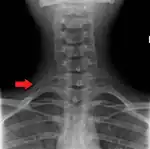

Variations in the number of ribs occur. About 1 in 200–500 people have an additional cervical rib, and there is a female predominance.[12] Intrathoracic supernumerary ribs are extremely rare.[13] The rib remnant of the 7th cervical vertebra on one or both sides is occasionally replaced by a free extra rib called a cervical rib, which can mechanically interfere with the nerves (brachial plexus) going to the arm.

X-ray image of a human chest, with ribs labelled